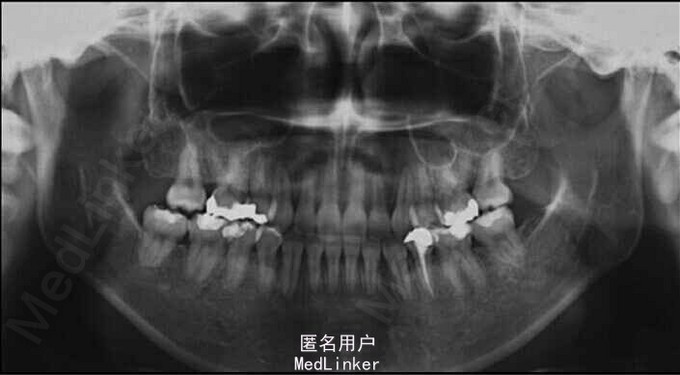

面部:凸面型,上下唇前突,上唇E线前3.5mm,下唇E线前9.5mm,闭唇时口周肌肉紧张。口内检查:双侧尖牙磨牙I类关系,左侧7锁合,覆盖4.5mm,覆合1mm,中线正,上颌拥挤度12.5mm,下颌拥挤度8.2mm。全景片示4个第三磨牙均阻生,怀疑上颌第二磨牙远中面因8阻生有牙根吸收,下颌8近中倾斜阻生更严重,右下6、左下4和5都行了RCT并大面积充填。头影测量示骨性I类,高角,下切牙唇倾。无TMJ症状,只是咀嚼测试时,右侧(非锁合侧)较左侧速度更快且更稳定。

诊断:安氏II类1分类,双颌前突,牙列严重拥挤,左下7锁合,双侧上7牙根吸收,四颗第三磨牙阻生 治疗目标:减少唇的突度及前牙拥挤,扶正4颗阻生的第三磨牙,达到良好的面部美观和功能咬合。 治疗:上颌拔除2颗5和2颗7(不拔4的原因为左上4为正常牙,左上5大面积充填;右上4形态较右上5好。因拔除了坏牙保留了健康牙齿,但是拔5不利于前牙的内收,所以于上后牙56之间植入了支抗钉加强支抗,辅助内收前牙。拔7原因为两颗7远中面均有牙根吸收且有大面积充填),下颌左侧拔除5和7(左下5根管治疗且根尖阴影,拔除左下7原因为严重锁合,改正困难且容易导致上下磨牙的伸长加重II类高角面型),右侧拔除根管治疗且大面积充填后的6;分别竖直4颗近中倾斜阻生的8,整个疗程39个月,四颗8成功的代替6或7。双侧I类尖牙关系,左侧磨牙I类关系,右侧磨牙完全远中关系。唇突度改善,全景片可见达到可接受的牙根平行度,4个8完全萌出直立。以前因为锁合导致的两侧咬合不对称没有了。